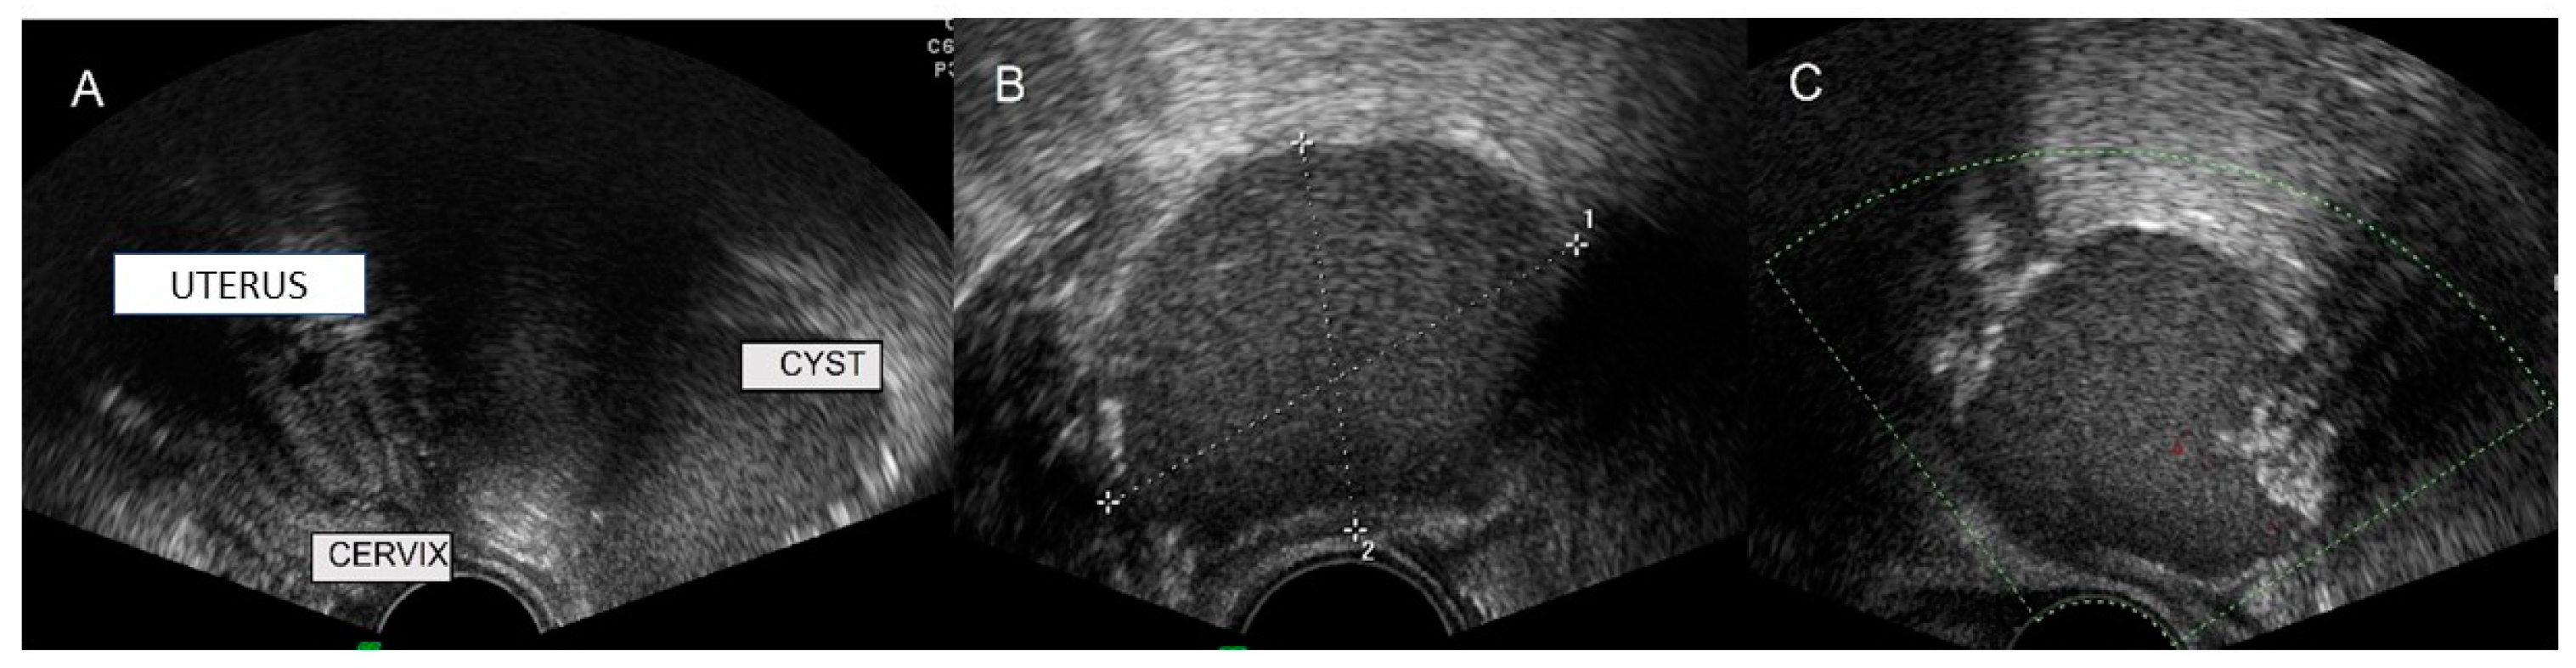

6.1. Tarlov Cyst